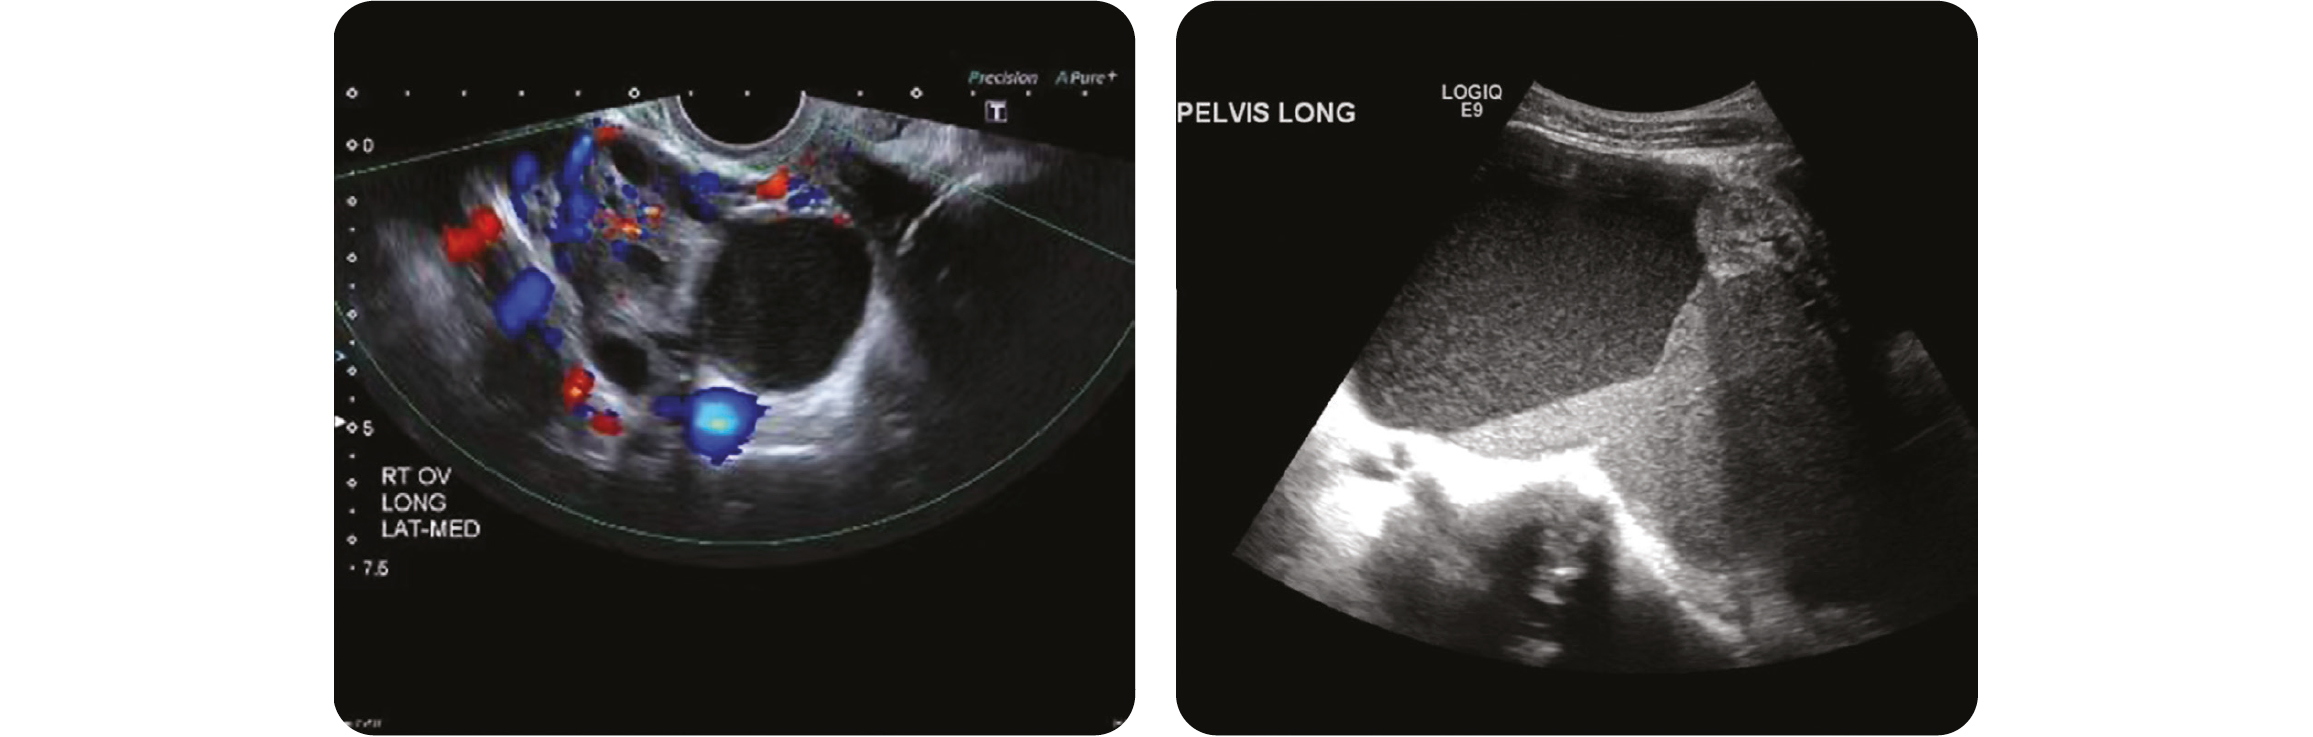

L'aspect d'endométriome a une présentation typique en échographie. On retrouve une formation kystique homogène hypoéchogène avec un fin picté échogène, sans paroi propre, amorphe et avasculaire siège parfois de caillot hyperéchogène curviligne déclive.

Source : Radiopedia